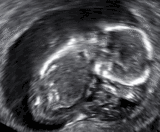

Diagnosis

In the case of blood loss, pain, or both, transvaginal ultrasound is performed. If a viable intrauterine pregnancy is not found with ultrasound, blood tests (serial βHCG tests) can be performed to rule out ectopic pregnancy, which is a life-threatening situation.[90][91]

A miscarriage may be confirmed by an obstetric ultrasound and by the examination of the passed tissue. When looking for microscopic pathologic symptoms, one looks for the products of conception. Microscopically, these include villi, trophoblast, fetal parts, and background gestational changes in the endometrium. When chromosomal abnormalities are found in more than one miscarriage, genetic testing of both parents may be done.[92]